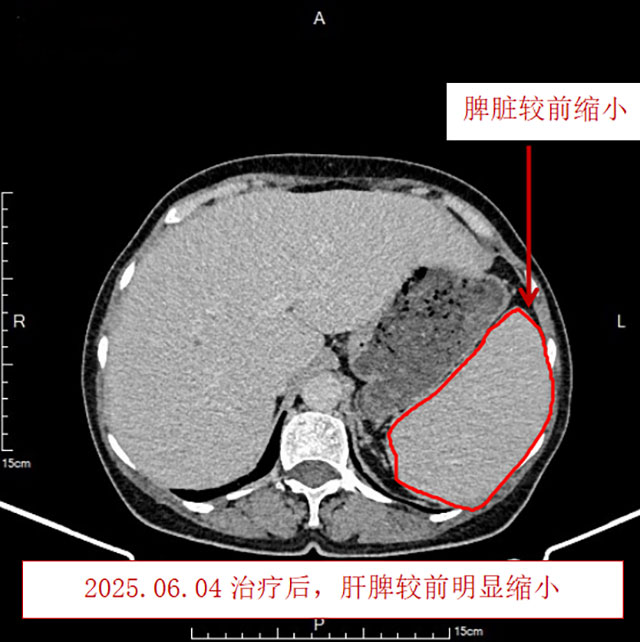

治疗后血小板恢复正常,心累、气促、乏力、汗多、潮热、双下肢水肿等症状均缓解,复查胸腹部CT发现淋巴结、肝脏、脾脏均较前明显缩小,复查骨髓未见异常B淋巴细胞。

3月9日,治疗正式开始,首次化疗前输血3次纠正贫血,随后每3周一次,共6个周期。整个治疗过程曾婆婆不良反应轻微,无恶心、呕吐,短时间出现厌油、味觉减退的情况,中量脱发,无发热、感染、疼痛、心慌、便秘、腹泻、手足麻木等症状。期间使用中医药治疗增效减毒,口服中药汤剂,益气养血、扶正驱邪;再使用温胃止呕方穴位贴敷、艾灸穴位止吐等,治疗效果明显。